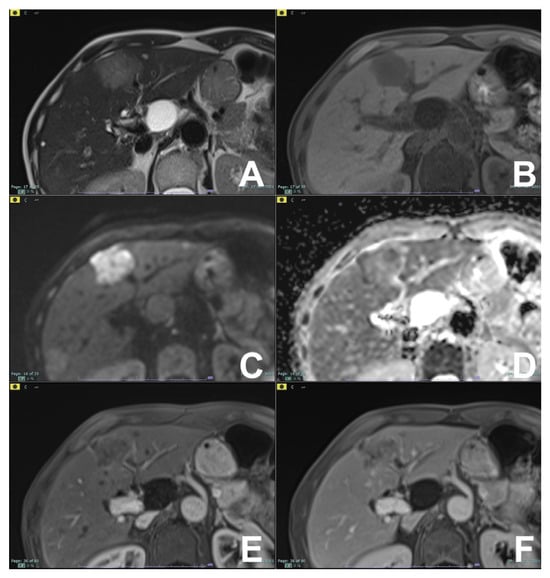

| Cirrhotic liver: characterization of FLL/Follow-up after treatment | HASTE T2 | AXIAL | -- | -- | Anatomy and liquids analysis |

| INDICATIONS: MRI is the technique of choice in young patients and pregnant women after a unclear US finding. Moreover, it is useful even after a CT with undefined diagnosis for all patients. | HASTE T2 | CORONAL | -- | -- | Anatomy and liquids analysis |

| DWI b 0–50–400–800 | AXIAL | -- | -- | High signal in b 800 suspicious for HCC | |

| GRE T1 IN/OUT | AXIAL | -- | -- | Steatosis | |

| GRE T1 3D DYNAMIC | AXIAL | PRE-ART 25″-PORTAL 70″-LATE 180″ | YES (if the lesion shows atypical enhancement) | Hypointensity in HBP suspicious for HCC | |